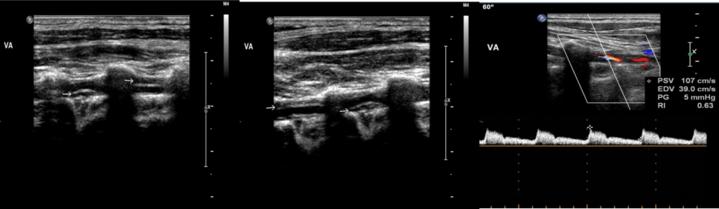

血管超声表现为椎动脉管壁增厚,管腔全程狭窄,诊断椎动脉夹层

头颈一体血管超声显示罗女士的颅外段椎动脉全程管壁不规则增厚,导致管腔全程狭窄,罗女士被诊断为颅外段椎动脉夹层。一般椎动脉夹层与外部创伤有重要关系,许佳音便询问罗女士:“最近有做颈部按摩吗?”罗女士表示自己并不喜欢按摩,只是一个月前打过一通两个小时的电话,打完电话后便开始出现头晕的症状。